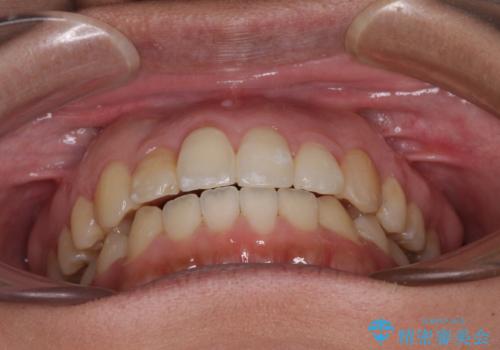

- 上下のデコボコを改善したいとのことで来院された患者様です。

近々妊娠する予定であり、極力短期間で治療したいとのことで、ワイヤー装置による非抜歯矯正治療を行うこととしました。